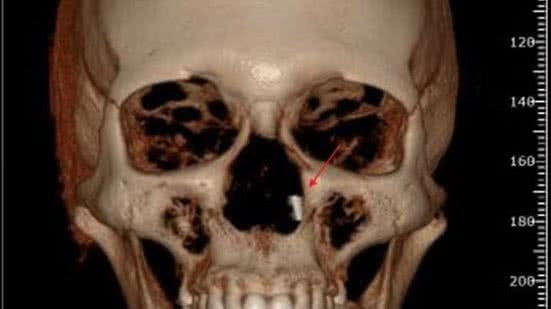

Ao decidir procurar um dentista com quem já havia se consultado, no resultado de um raio-x panorâmico a que foi submetida foi identificado um objeto metálico que condizia, pelo formato e tamanho, com a broca.

Ela foi orientada a procurar um cirurgião bucomaxilo para a retirada do material, que estava localizada na parte posterior do nariz, e em seguida, foi encaminhada a um otorrinolaringologista. Na cirurgia, foi submetida a anestesia geral, mas a broca não foi encontrada.

De acordo com a decisão do juiz Arthur Eduardo Magalhães Ferreira, era incontestável a presença do objeto após o procedimento realizado pelos dentistas.